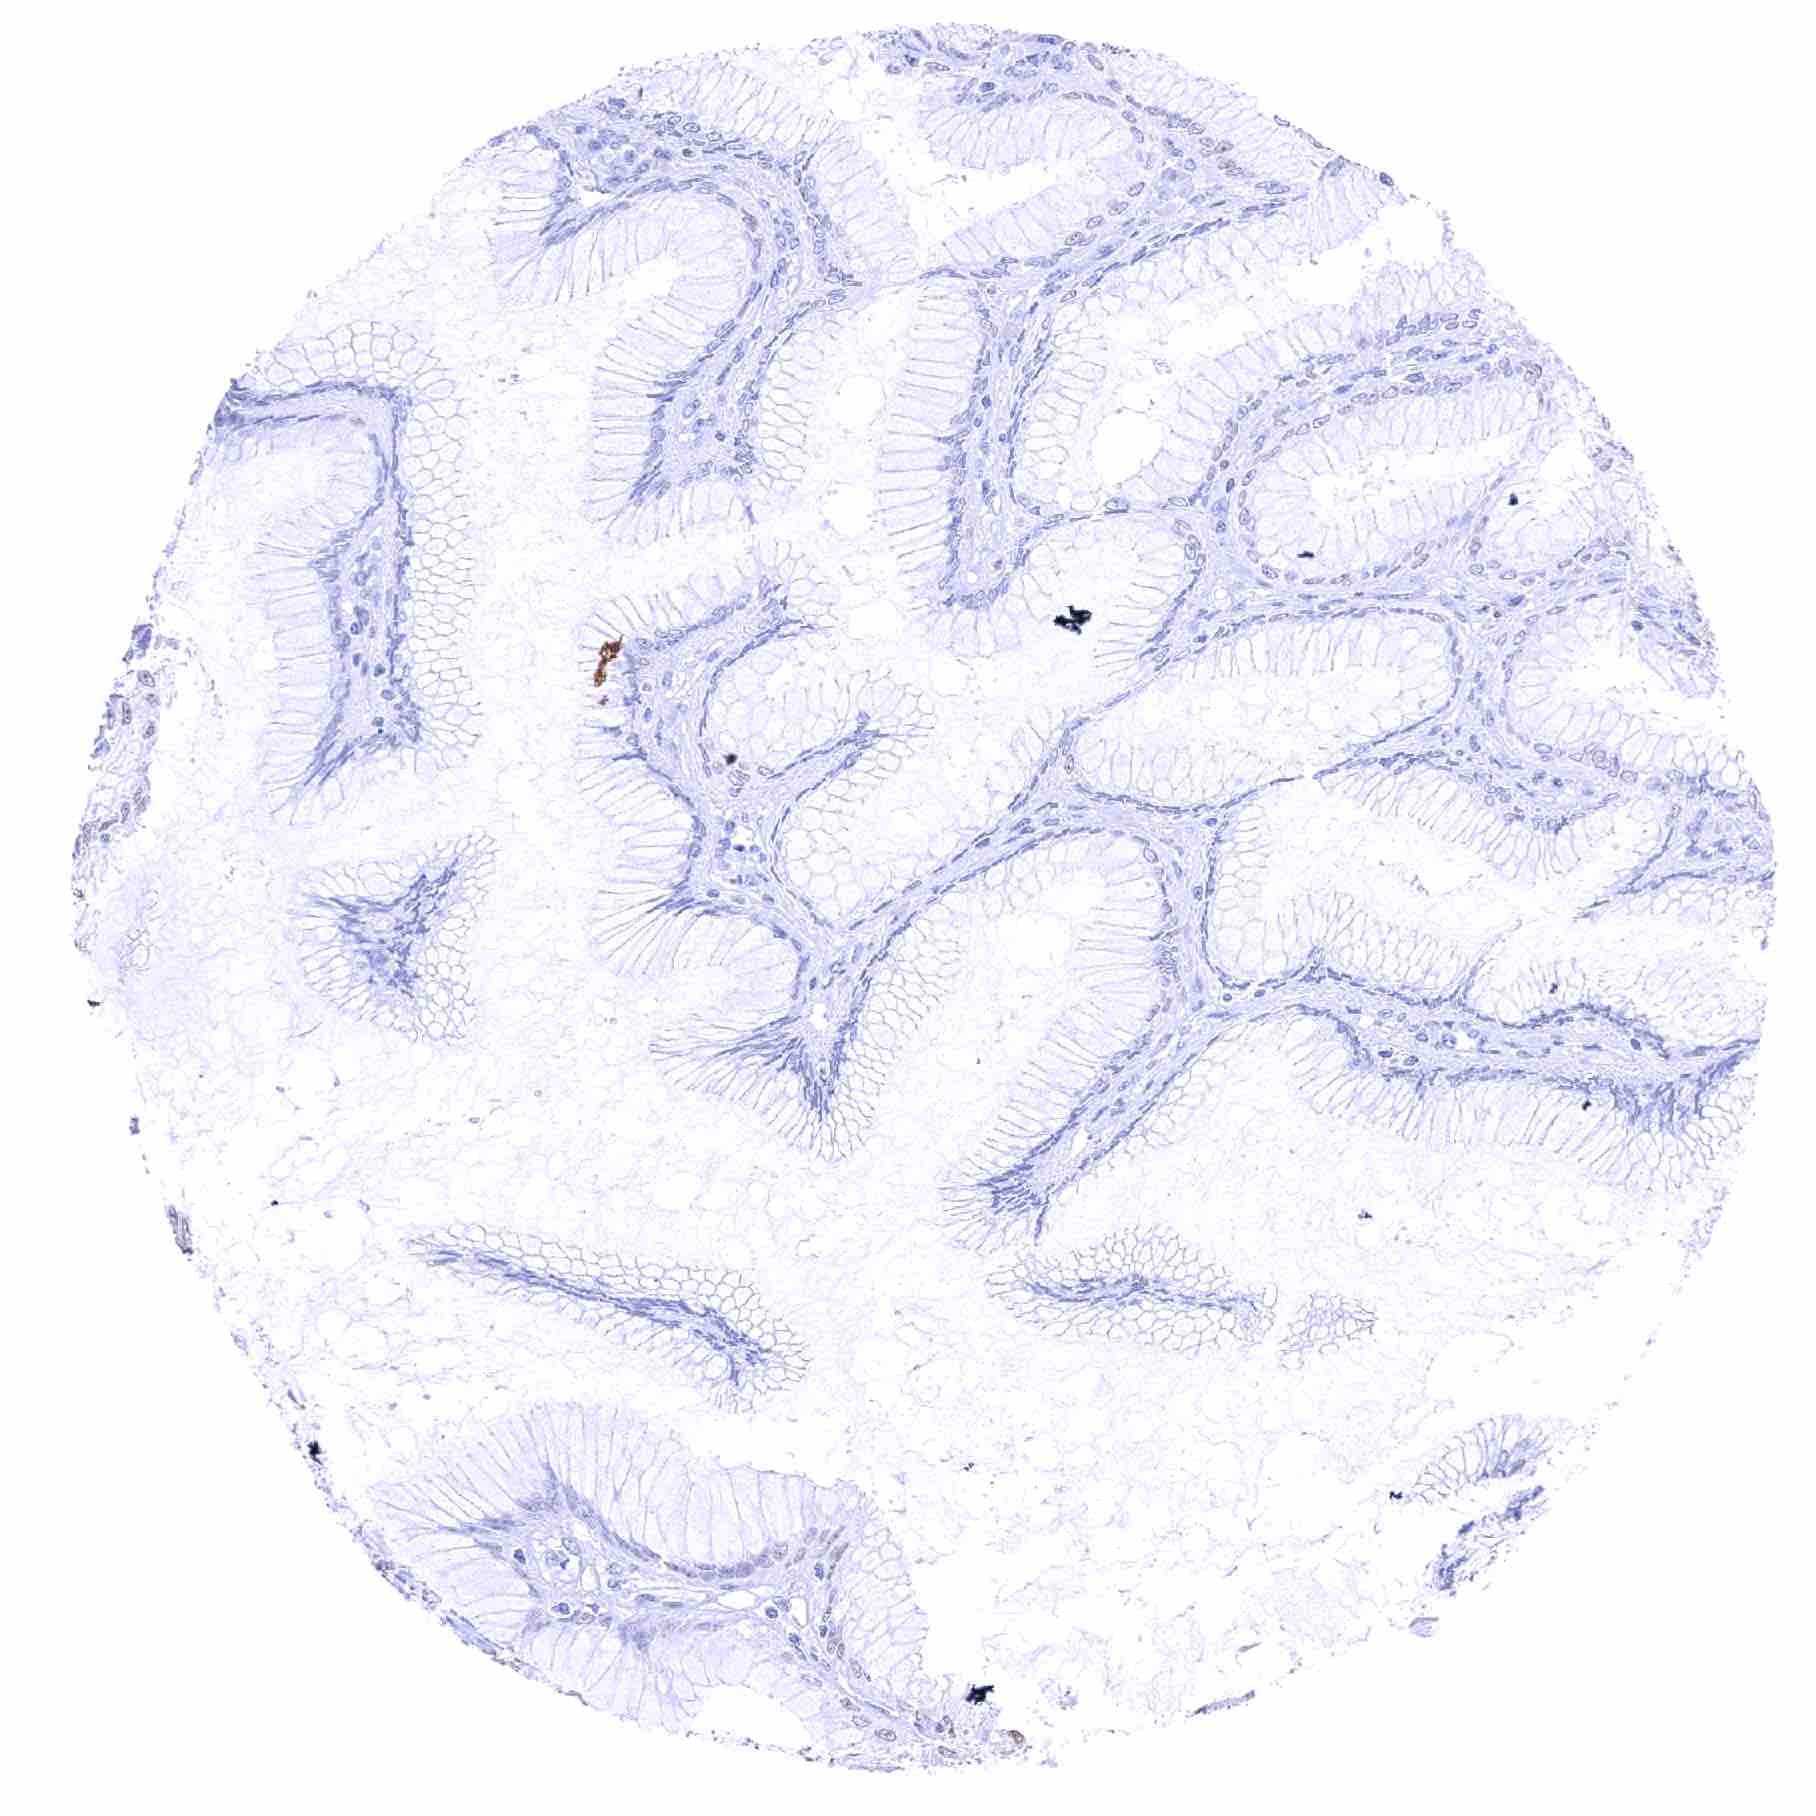

Stomach, antrum – Significant SOX2 staining of a fraction of glandular cells

Stomach, antrum